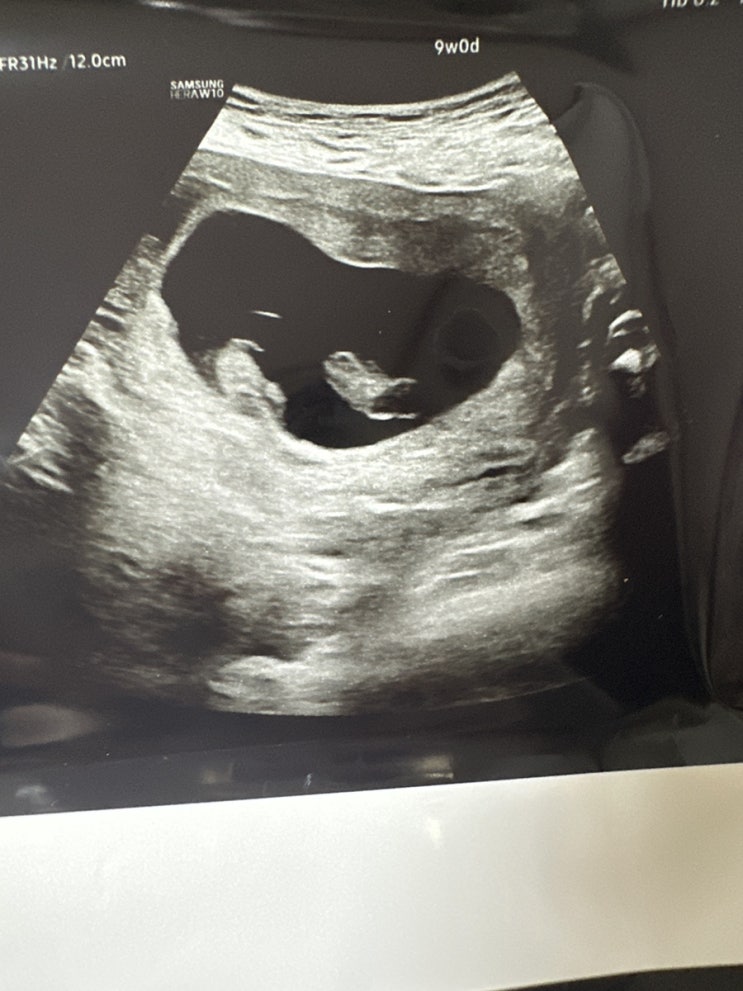

일란성 쌍둥이 임신 초기 증상 / 오르락내리락 입덧 & 쑥쑥 크는 첫찌, 자궁경부 상피내암 MRI 예정

임신일상기록 차근차근 쌓아나가기 작년(2022년) 10월에 첫째를 출산하고 7개월 후 임신을 하게 되었다. ㅎ...

일란성 쌍둥이 자연 임신+자궁경부암, 잘될거야 ?

블태기 극뽁? ㅎㅎ 쓰고싶을 땐 포스팅 하는걸로 결정할래요 ㅋㅋ꾸준한 건 아직 어렵지만 차근차근 이어나...